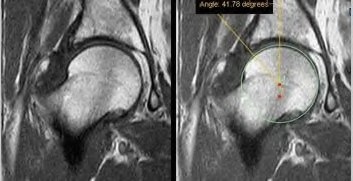

A surgeon is performing a primary TKA and decides to use the surgical epicondylar axis (SEA) to set the rotation of the femoral component. Which of the following best defines the SEA?

Explanation